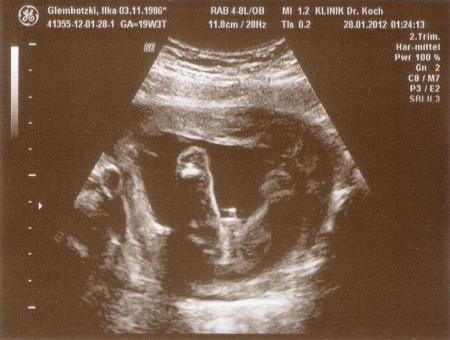

Hallo ihr lieben, ich muss euch sagen- ich bin total verliebt! Unseren Krümmel gehts super- zu 90 % wirds ein kleiner Junge Mein Gefühl hat mir zwar ein Mädchen "versprochen"- aber so haben wir halt erst mal einen großen Bruder... *grins* Unser Baby war total aktiv und hat die ganze Zeit rumgezappelt und an seinem Fuß genuckelt.... SOOOOOO SÜß.... Gemessen werden konnte es nicht genau- lag nur gekrümmt- müsste aber so ca 15-16 cm groß sein Bin sooo froh das alles ok ist!

Bild zu FA Bericht - Forum für Juli - Mamis